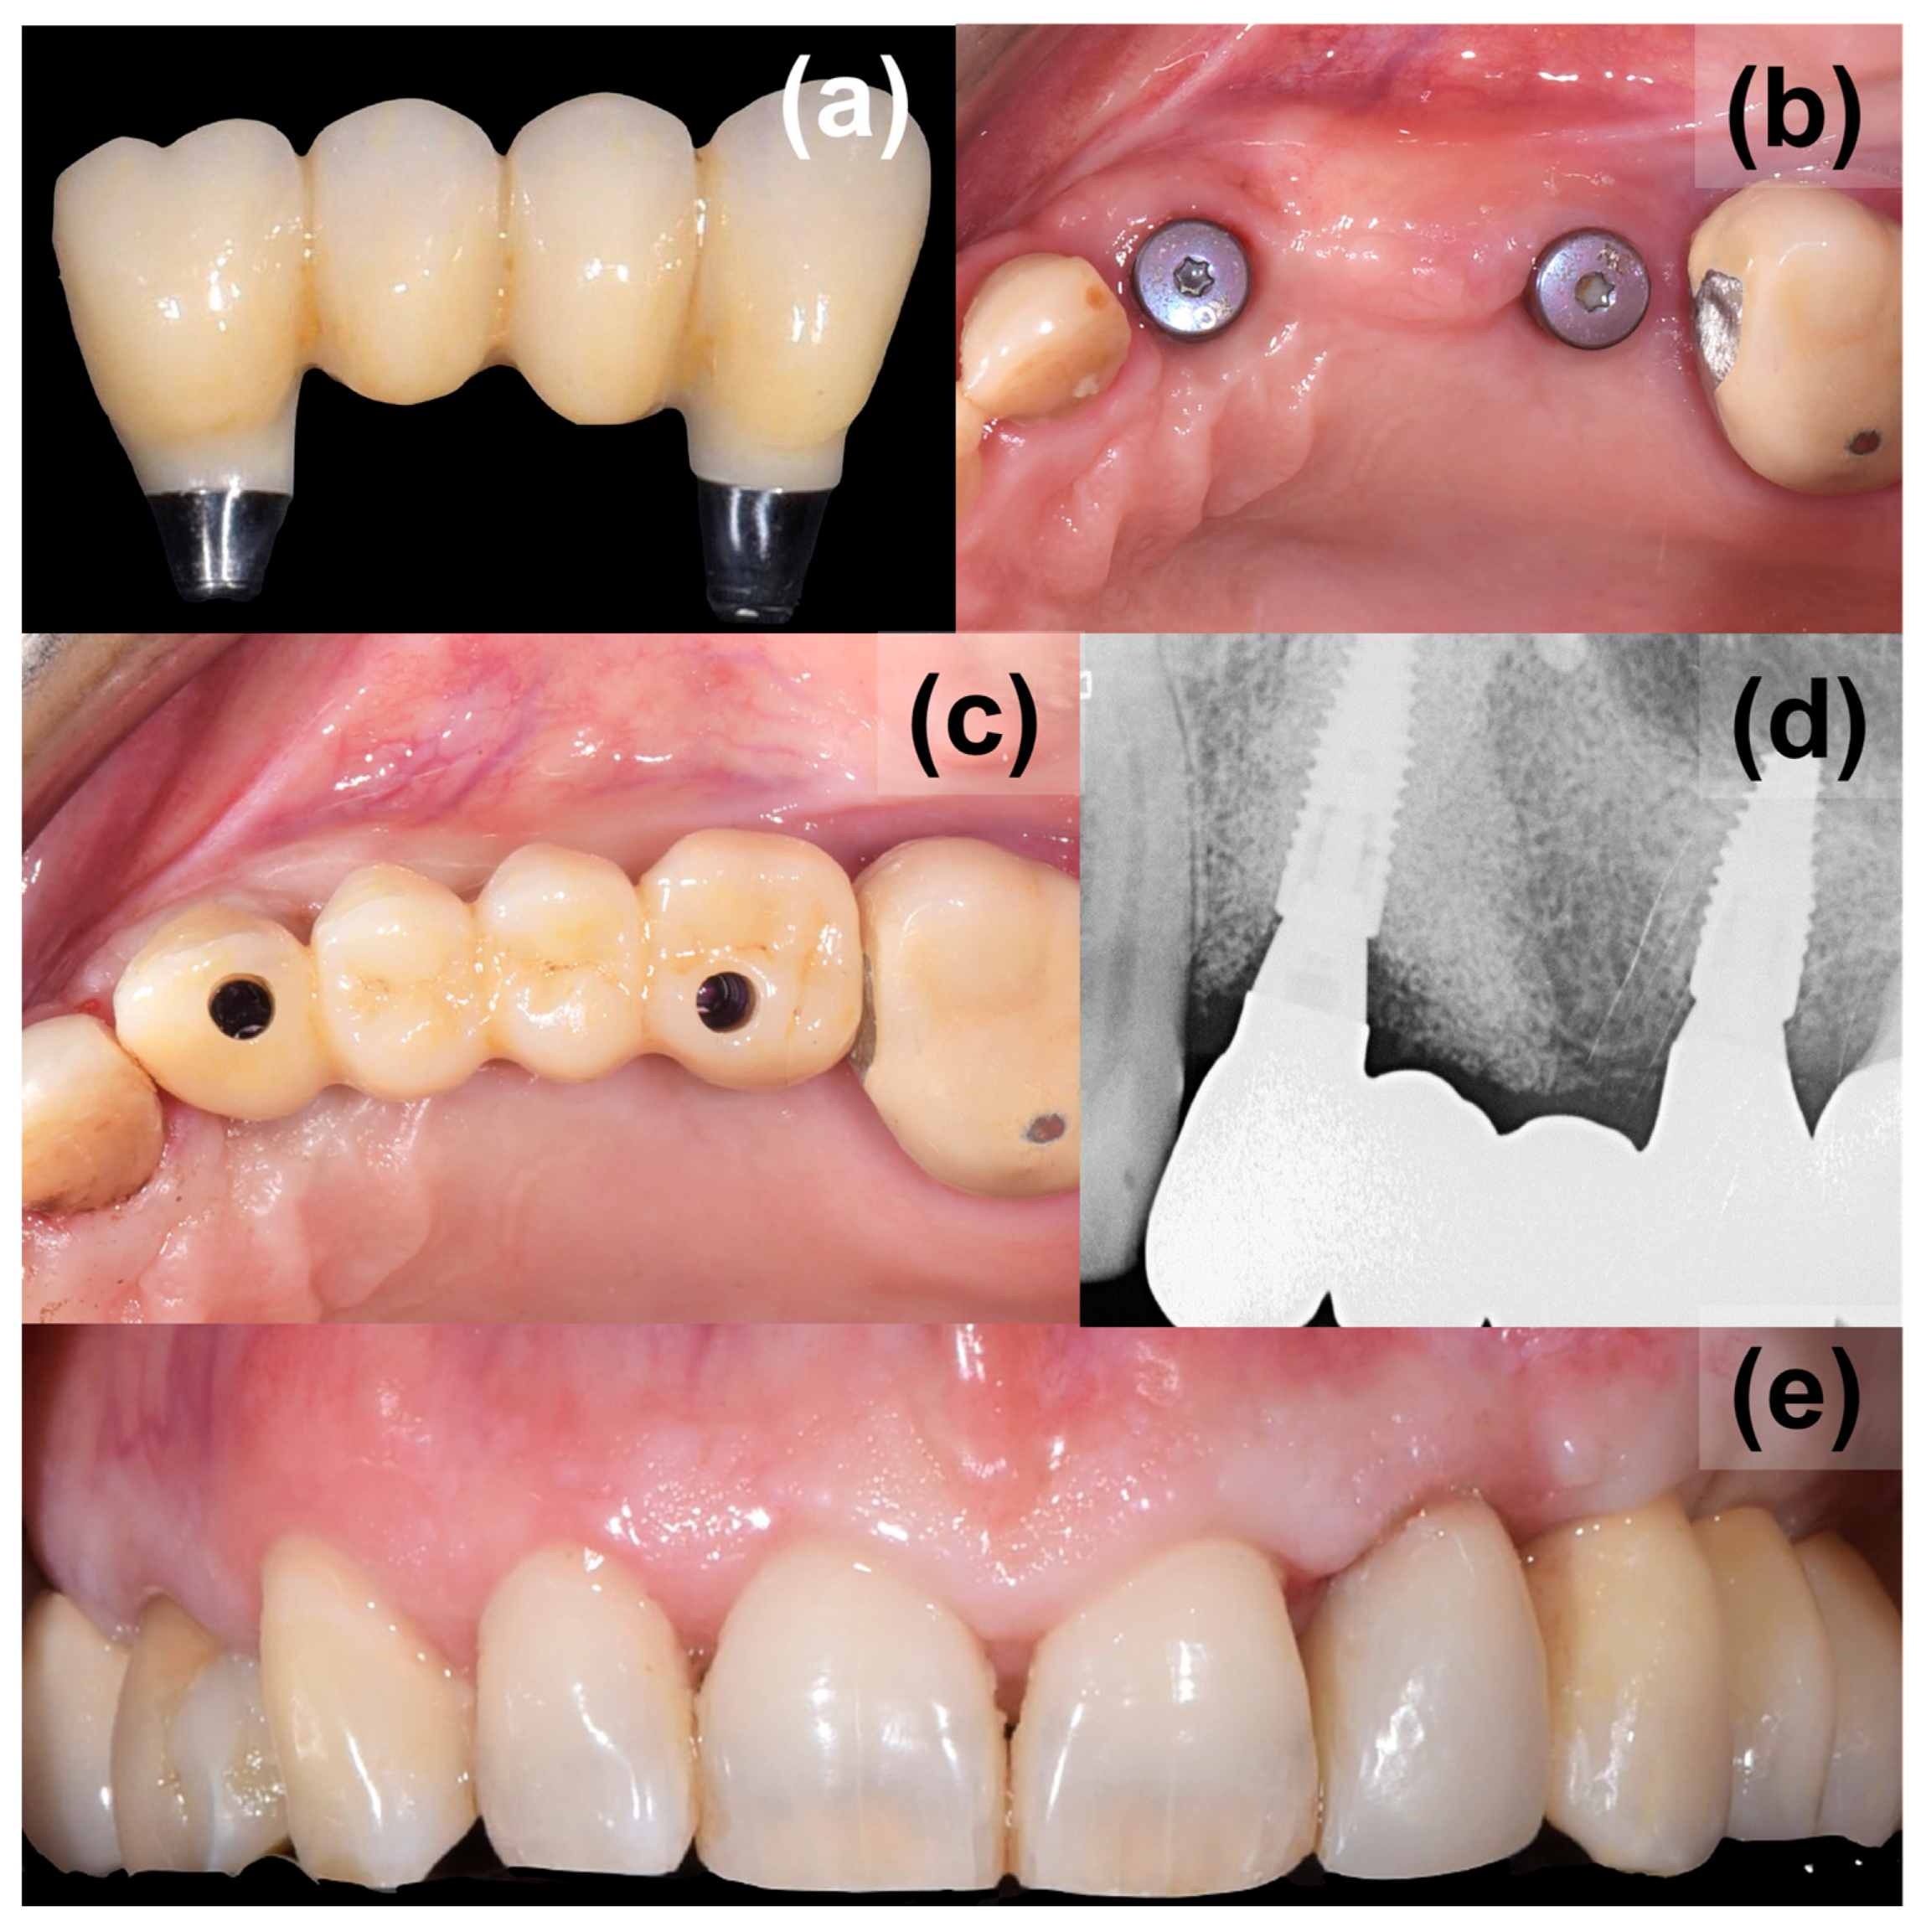

Figure 5.

Application of final prosthesis, (a) a screw retained three-unit bridge made of monolithic zirconia, (b) final appearance of augmented site, (c) applied bridge, (d) control X-ray, (e) final aesthetics from the buccal view.